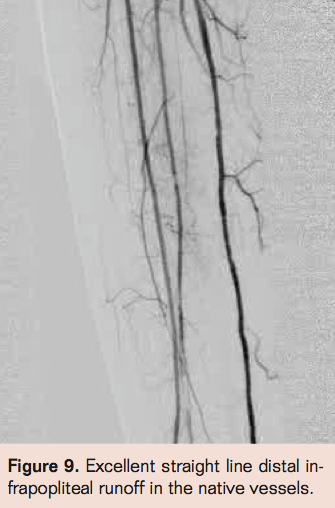

- Angiography utilizing ipsilateral obique projection to visualize graft origin if possible (may not visualize). Evaluate outflow as well (Figure 1).

- Laser thrombectomy at 1 mm/sec. with the 2.3 mm probe (Figures 4-9)